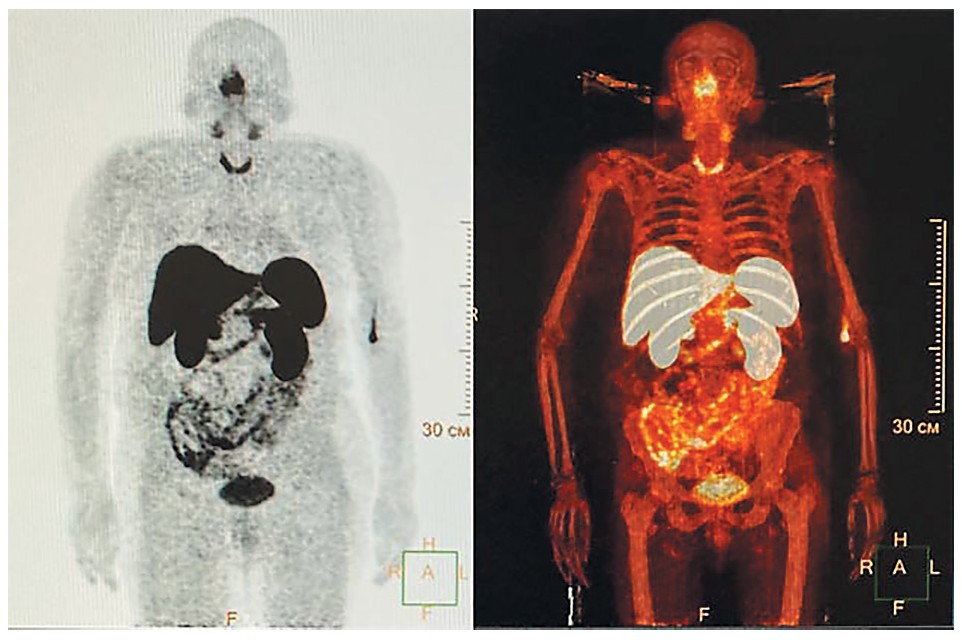

Для поиска первичного эктопического очага гиперсекреции АКТГ пациентка направлена на проведение комбинированной позитронно-эмиссионной и рентгеновской КТ (ПЭТ/КТ) с 68Ga-DOTA-TATE – участков накопления радиофармпрепарата не обнаружено, описано негативное образование в S1/2 доли левого легкого (гамартома?), негативные неравномерные участки уплотнения в S6 правого и S9 левого легкого (рис. 3).

Рис. 3. ПЭТ-КТ с 68Ga-DOTA-TATE, 6 мес после двусторонней адреналэктомии. Признаков 68Ga-DOTA-TATE-позитивной опухоли не выявлено; негативное образование в S1/2 доли левого легкого (гамартома?); негативные неравномерные участки уплотнения S6 правого и S9 левого легкого; негативное образование в правой доле щитовидной железы; кисты почек.

Fig. 3. Positron emission tomography – computed tomography with 68Ga-DOTA-TATE, 6 months after bilateral adrenalectomy. No signs of 68Ga-DOTA-TATE-positive tumor; negative formation in S 1/2 lobe of left lung (hamartoma?); negative irregular areas of consolidation in S6 of right and S9 of left lung; negative formation in right lobe of thyroid gland; renal cysts.

После стабилизации состояния пациентки продолжен диагностический поиск первичного очага АКТГ-эктопии. При ПЭТ/КТ с 68Ga-DOTA-TATE не выявлено накопления радиофармпрепарата в каких-либо очагах, в том числе в левом легком. Этот метод обследования считается достаточно чувствительным для диагностики АКТГ-секретирующих нейроэндокринных внегипофизарных опухолей [14–16], хотя в последнее время обсуждаются преимущества применения 68Ga-DOTA-TATE при внелегочной локализации нейроэндокринных опухолей [17], а также комбинации методов ПЭТ/КТ с 68Ga-DOTA-TATE и 18F-FDG в диагностически сложных случаях, что позволяет повысить выявляемость АКТГ-эктопических опухолей до 90% случаев [14, 18]. Показано, что ПЭТ/КТ с 18F-FDG также может применяться в диагностике МР-негативных кортикотропином малых размеров1. Но в нашем случае дальнейшее обследование было приостановлено в связи с тем, что через 4 мес после операции зафиксировано значительное снижение уровня АКТГ. Такое возможно только после удаления источника гиперсекреции АКТГ, и этот факт стал основанием для поиска АКТГ-эктопического очага в удаленной ткани надпочечников. Концентрация АКТГ оставалась несколько повышенной, однако – с учетом двусторонней адреналэктомии в анамнезе – можно сказать, что уровень АКТГ соответствовал состоянию первичной надпочечниковой недостаточности [19].